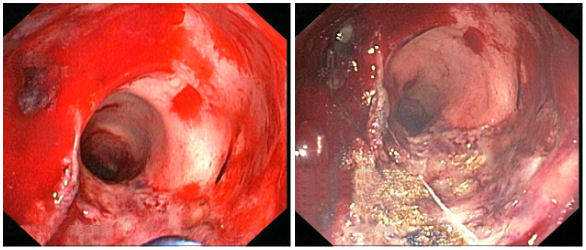

Examples for bleeding from other sources treated with APC are gastrointestinal vascular lesions [15], bleeding in the large intestine (colon) due to damage caused by radiotherapy (radiation proctritis, see Figure 7 [Fig. 7]) [16], and heavy bleeding of an infected bladder (haemorrhagic cystitis) [17].

Figure 7: Bleeding in the colon due to radiation proctritis (left) before and (right) after treatment with APC. Reproduced with kind permission of A. Eickhoff, Klinikum Ludwigshafen, Germany